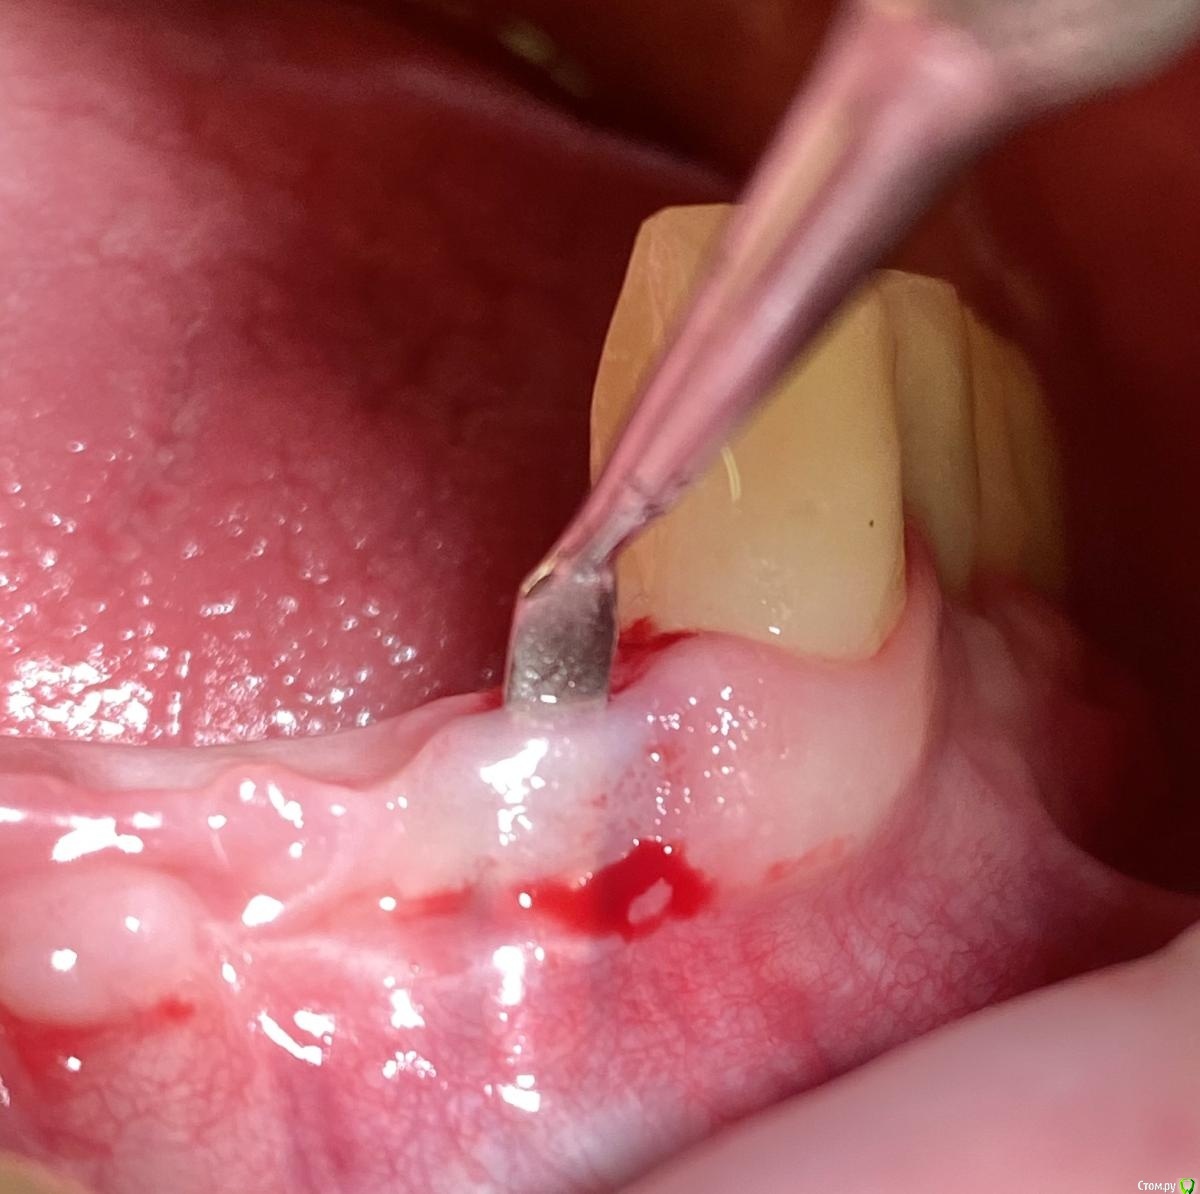

колесников Опубликовано 2 февраля, 2021 Поделиться Опубликовано 2 февраля, 2021 Я же писал,гладилка,скальпель15С,пинцет-вот все что нужно для работы. Правда тут был перионож,под углом в шахту не удавалось войти.Все хорошо у Вас. Надо подождать. Я думаю подрастёт. И ещё добавить . Расщеплять будет уже веселее. Красивый профиль сделали на реставрации. Но! Этот уступ 1мм! Он все портит. Или пилить юбку или брать высотой 3мм Ссылка на комментарий

колесников Опубликовано 6 февраля, 2021 Поделиться Опубликовано 6 февраля, 2021 Почему?Я просто не имею опыта с виста. просто тут перфорировать легко. В основании уздечки ткани вплетаются в основание гребня и тут же витки импланта,вход рассечь можно,а дальше при отслаивании инструмент скользнёт по виткам и уйдёт вверх-перфорация ,потом эта дыра расползается. Проще открутить реставрацию и войти через шахту. А вообще виста самый анатомический доступ 1 Ссылка на комментарий